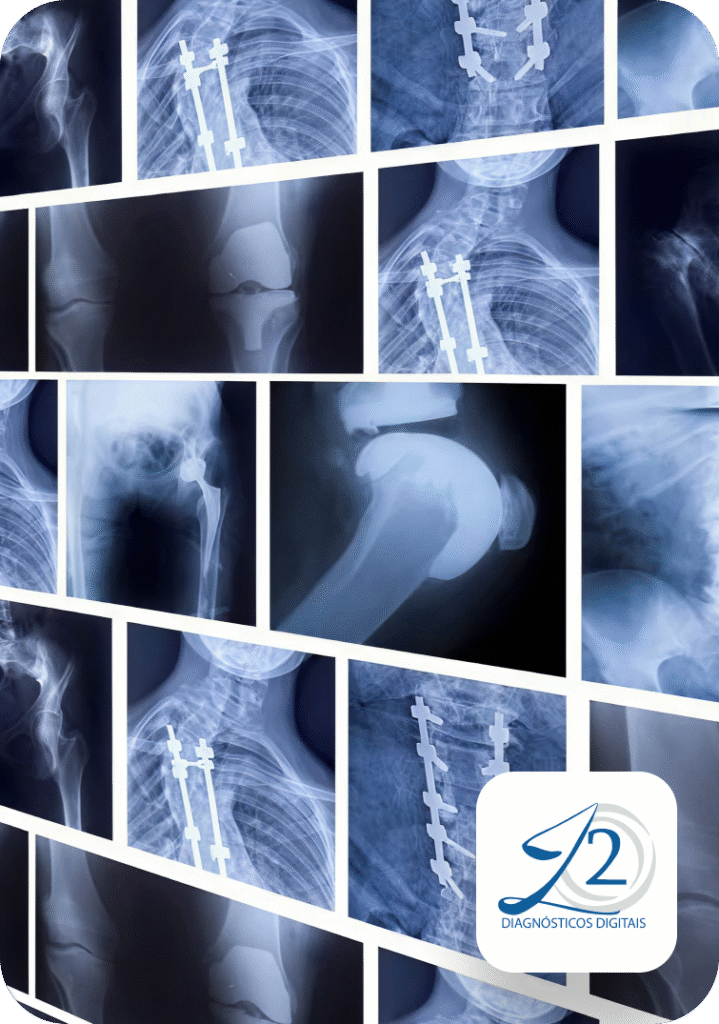

O Raio-X Digital é um exame versátil, rápido e indolor, sendo a principal ferramenta de apoio diagnóstico nas seguintes áreas:

Ortopedia e Traumatologia: Avaliação de fraturas, luxações, desgaste das articulações (artrose) e alterações na coluna vertebral.

Saúde Pulmonar (Tórax): Investigação minuciosa de pneumonias, derrames pleurais, nódulos e outras patologias do trato respiratório.

Acompanhamento Pós-operatório: Monitoramento da consolidação óssea e verificação do posicionamento exato de implantes e próteses.